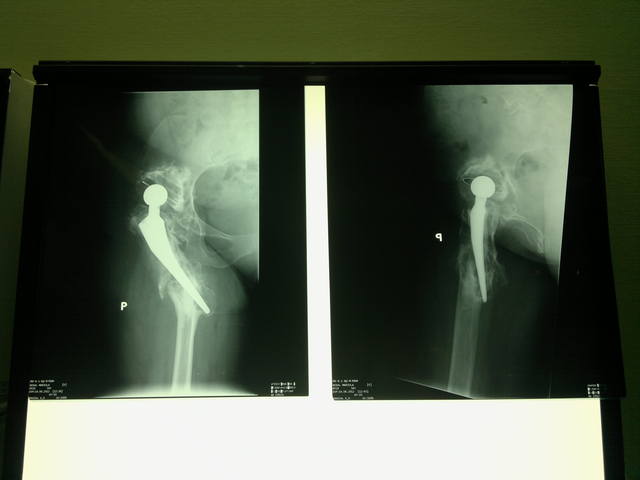

<br /><br />Женщина 54 года, оперирована с обеих сторон около 5 лет назад. Примерно 1 год назад получила перипротезные переломы с обеих сторон. Слева - выполнено ревизионное эндопротезирование. Справа - удален эндопротез, в плане - тотальное ревизионное эндопротезирование.<br /><br />Господа-протезисты, Ваши предложения в этом случае?<br /><br />